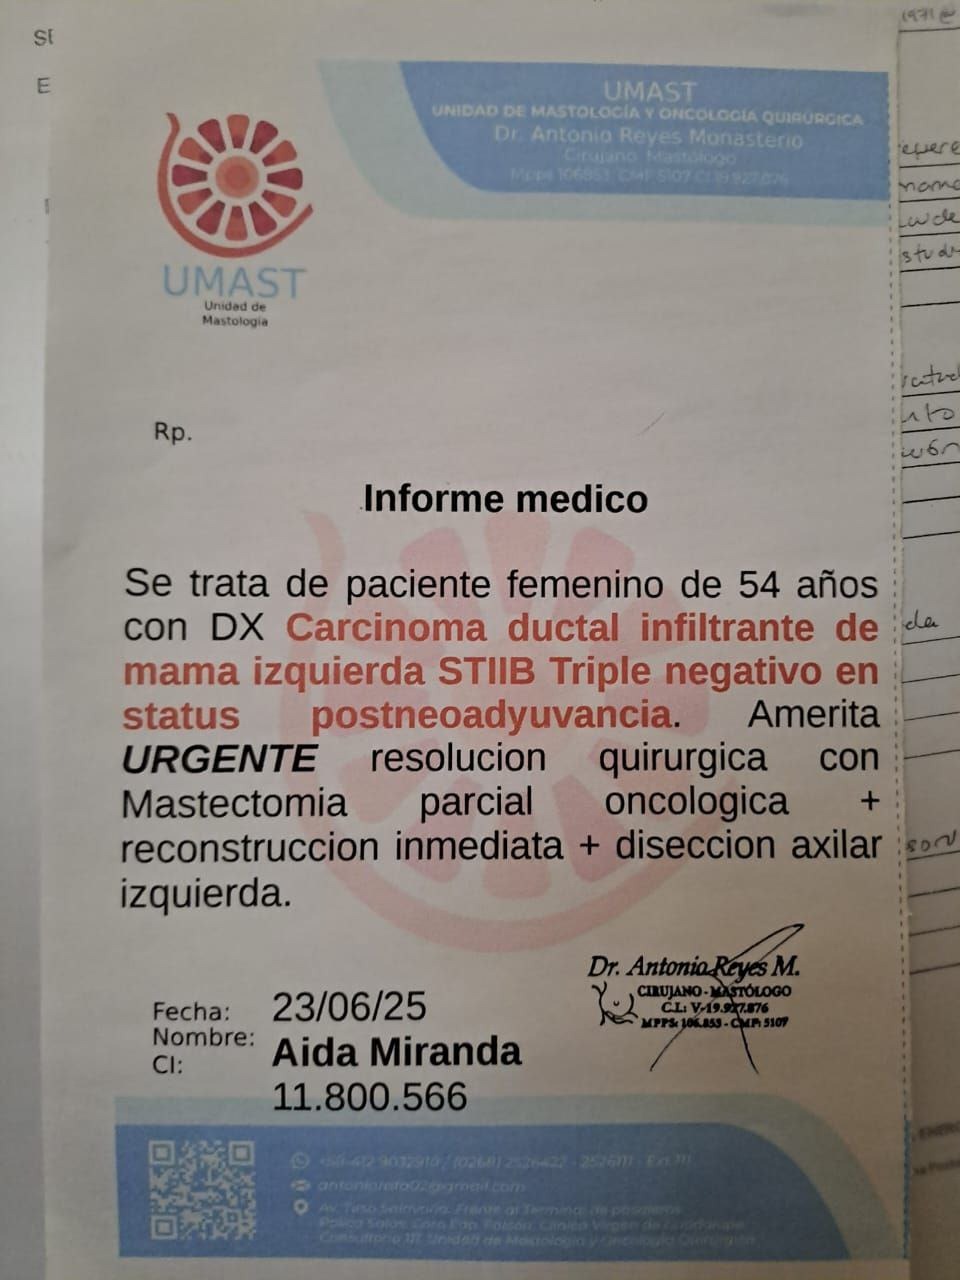

Luego de varios meses de lucha, de muchos obstáculos, dolores, oraciones, subidas y bajadas, ¡Aida ha logrado el objetivo poco a poco! Pero no lo ha hecho sola, ha estado acompañada por Dios, primeramente, por su familia, amigos, vecinos, personal medico, por cada uno de ustedes y ¡hasta desconocidos!. Estamos enormemente agradecidos por contar con el apoyo que nos han dado en esta situación tan difícil para todos, cada granito de arena ha sido muy importante para su proceso, se lograron hacer varios estudios importantes requeridos, se lograron varias consultas con especialistas, tratamientos y suplementos, gracias al aporte de cada uno.

Ya el primer gran paso fue dado, su quimioterapia. En este segundo paso, Aida esta apta para ser intervenida quirúrgicamente, luego de haber recibido sus ciclos de quimioterapia, que han sido duros, pero no imposibles, estamos recaudando para poder realizar su MASTECTOMIA PARCIAL ONCOLOGICA, RECONSTRUCCION Y DISECCION AXILAR IZQUIERDA.

Luego viene el tercer paso, Radioterapias, Es por esta razón que actualizamos nuestra historia, para seguir apoyándola en su recuperación total y pueda ser tocada esa campana que tanto queremos escuchar.

After several months of struggle, many obstacles, pain, prayers, ups and downs, Aida has slowly achieved her goal! But she hasn't done it alone; she's been accompanied by God, first and foremost by her family, friends, neighbors, medical staff, each and every one of you, and even strangers! We are incredibly grateful for the support you've given us during this difficult time for everyone. Every little bit has been crucial to her journey. We were able to complete several important tests, consult with specialists, and receive treatments and supplements, thanks to each and every one of your contributions.

The first big step has already been taken: her chemotherapy. In this second step, Aida is ready for surgery. After receiving her chemotherapy cycles, which have been difficult but not impossible, we are raising funds to support her oncological partial mastectomies, reconstruction, and left axillary dissection.

Then comes the third step: radiation therapy. This is why we are updating our story to continue supporting her in her full recovery and to help ring that bell we so desperately want to hear.